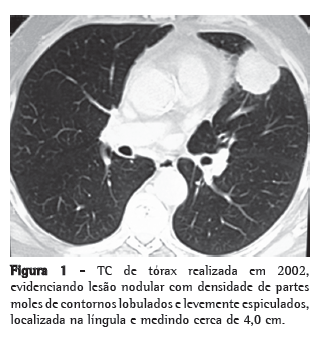

Relato de casoPaciente masculino de 71 anos de idade, com antecedente de lobectomia superior esquerda com ressecção do pericárdio por invasão local e linfadenectomia mediastinal há cinco anos (Figura 1). Estadiamento patológico IIB (T3N0M0). No seguimento com exame de imagem, achado de lesão pulmonar contralateral-0,8 cm no segmento superior do lobo inferior direito-não presente nos controles anteriores (Figura 2).